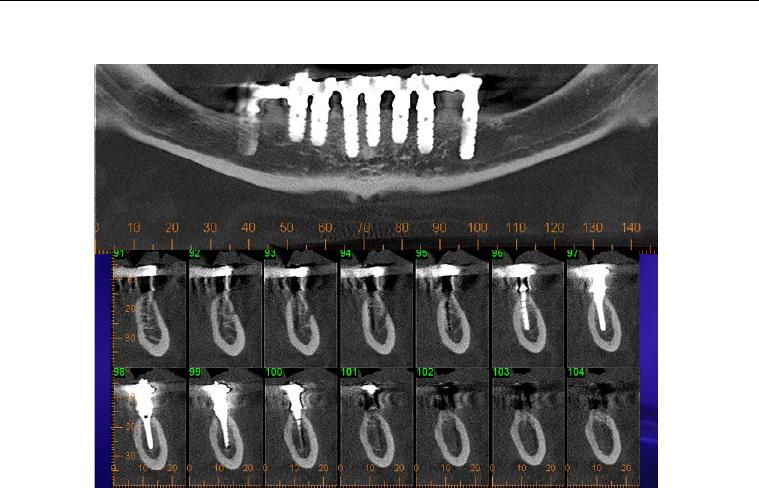

Foi no intuito de transpor estas dificuldades que se idealizou o sistema de

implante inicialmente conhecido como Wedge (figura 1) e que, após dez anos de